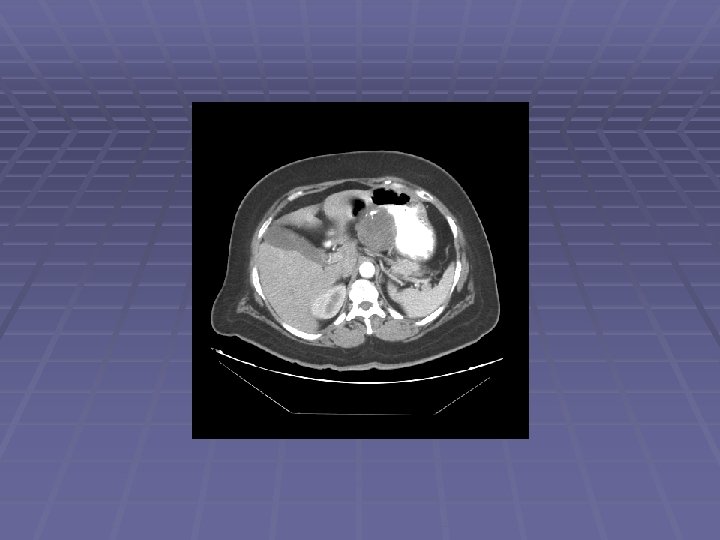

Liver Mass

FNA of Liver Mass

EUS Evaluation of Left Lobe of Liver